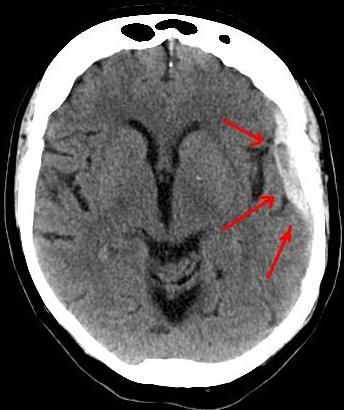

Subdural Hematoma

An accumulation of blood on the surface of the brain is known as a subdural hematoma.

Subdural hematomas develop after trauma because the bridging veins between the dura and arachnoid rupture.

Radiology of subdural hematomas reveal a lesion with a crescent shape.